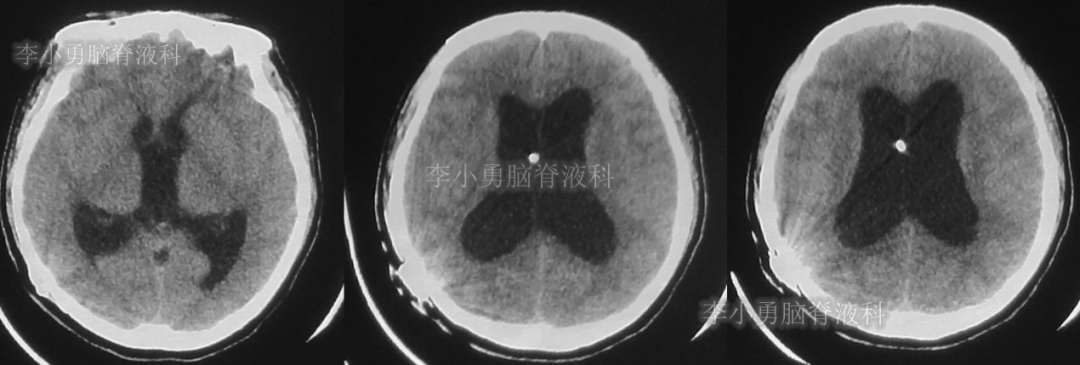

患者于2018年1月29日,突发头痛、头晕、恶心、呕吐,并高热40度。在当地医院门诊输入4天抗生素后发热缓解,但出现了双眼不能上视(眼球不能向上看)。5天后即2018年2月3日,在当地的第1家医院:浙江省海宁市某医院行头颅CT(图-1)发现脑室扩张,当地医院诊断为“梗阻性脑积水”。

图-1:2018年2月3日头颅CT